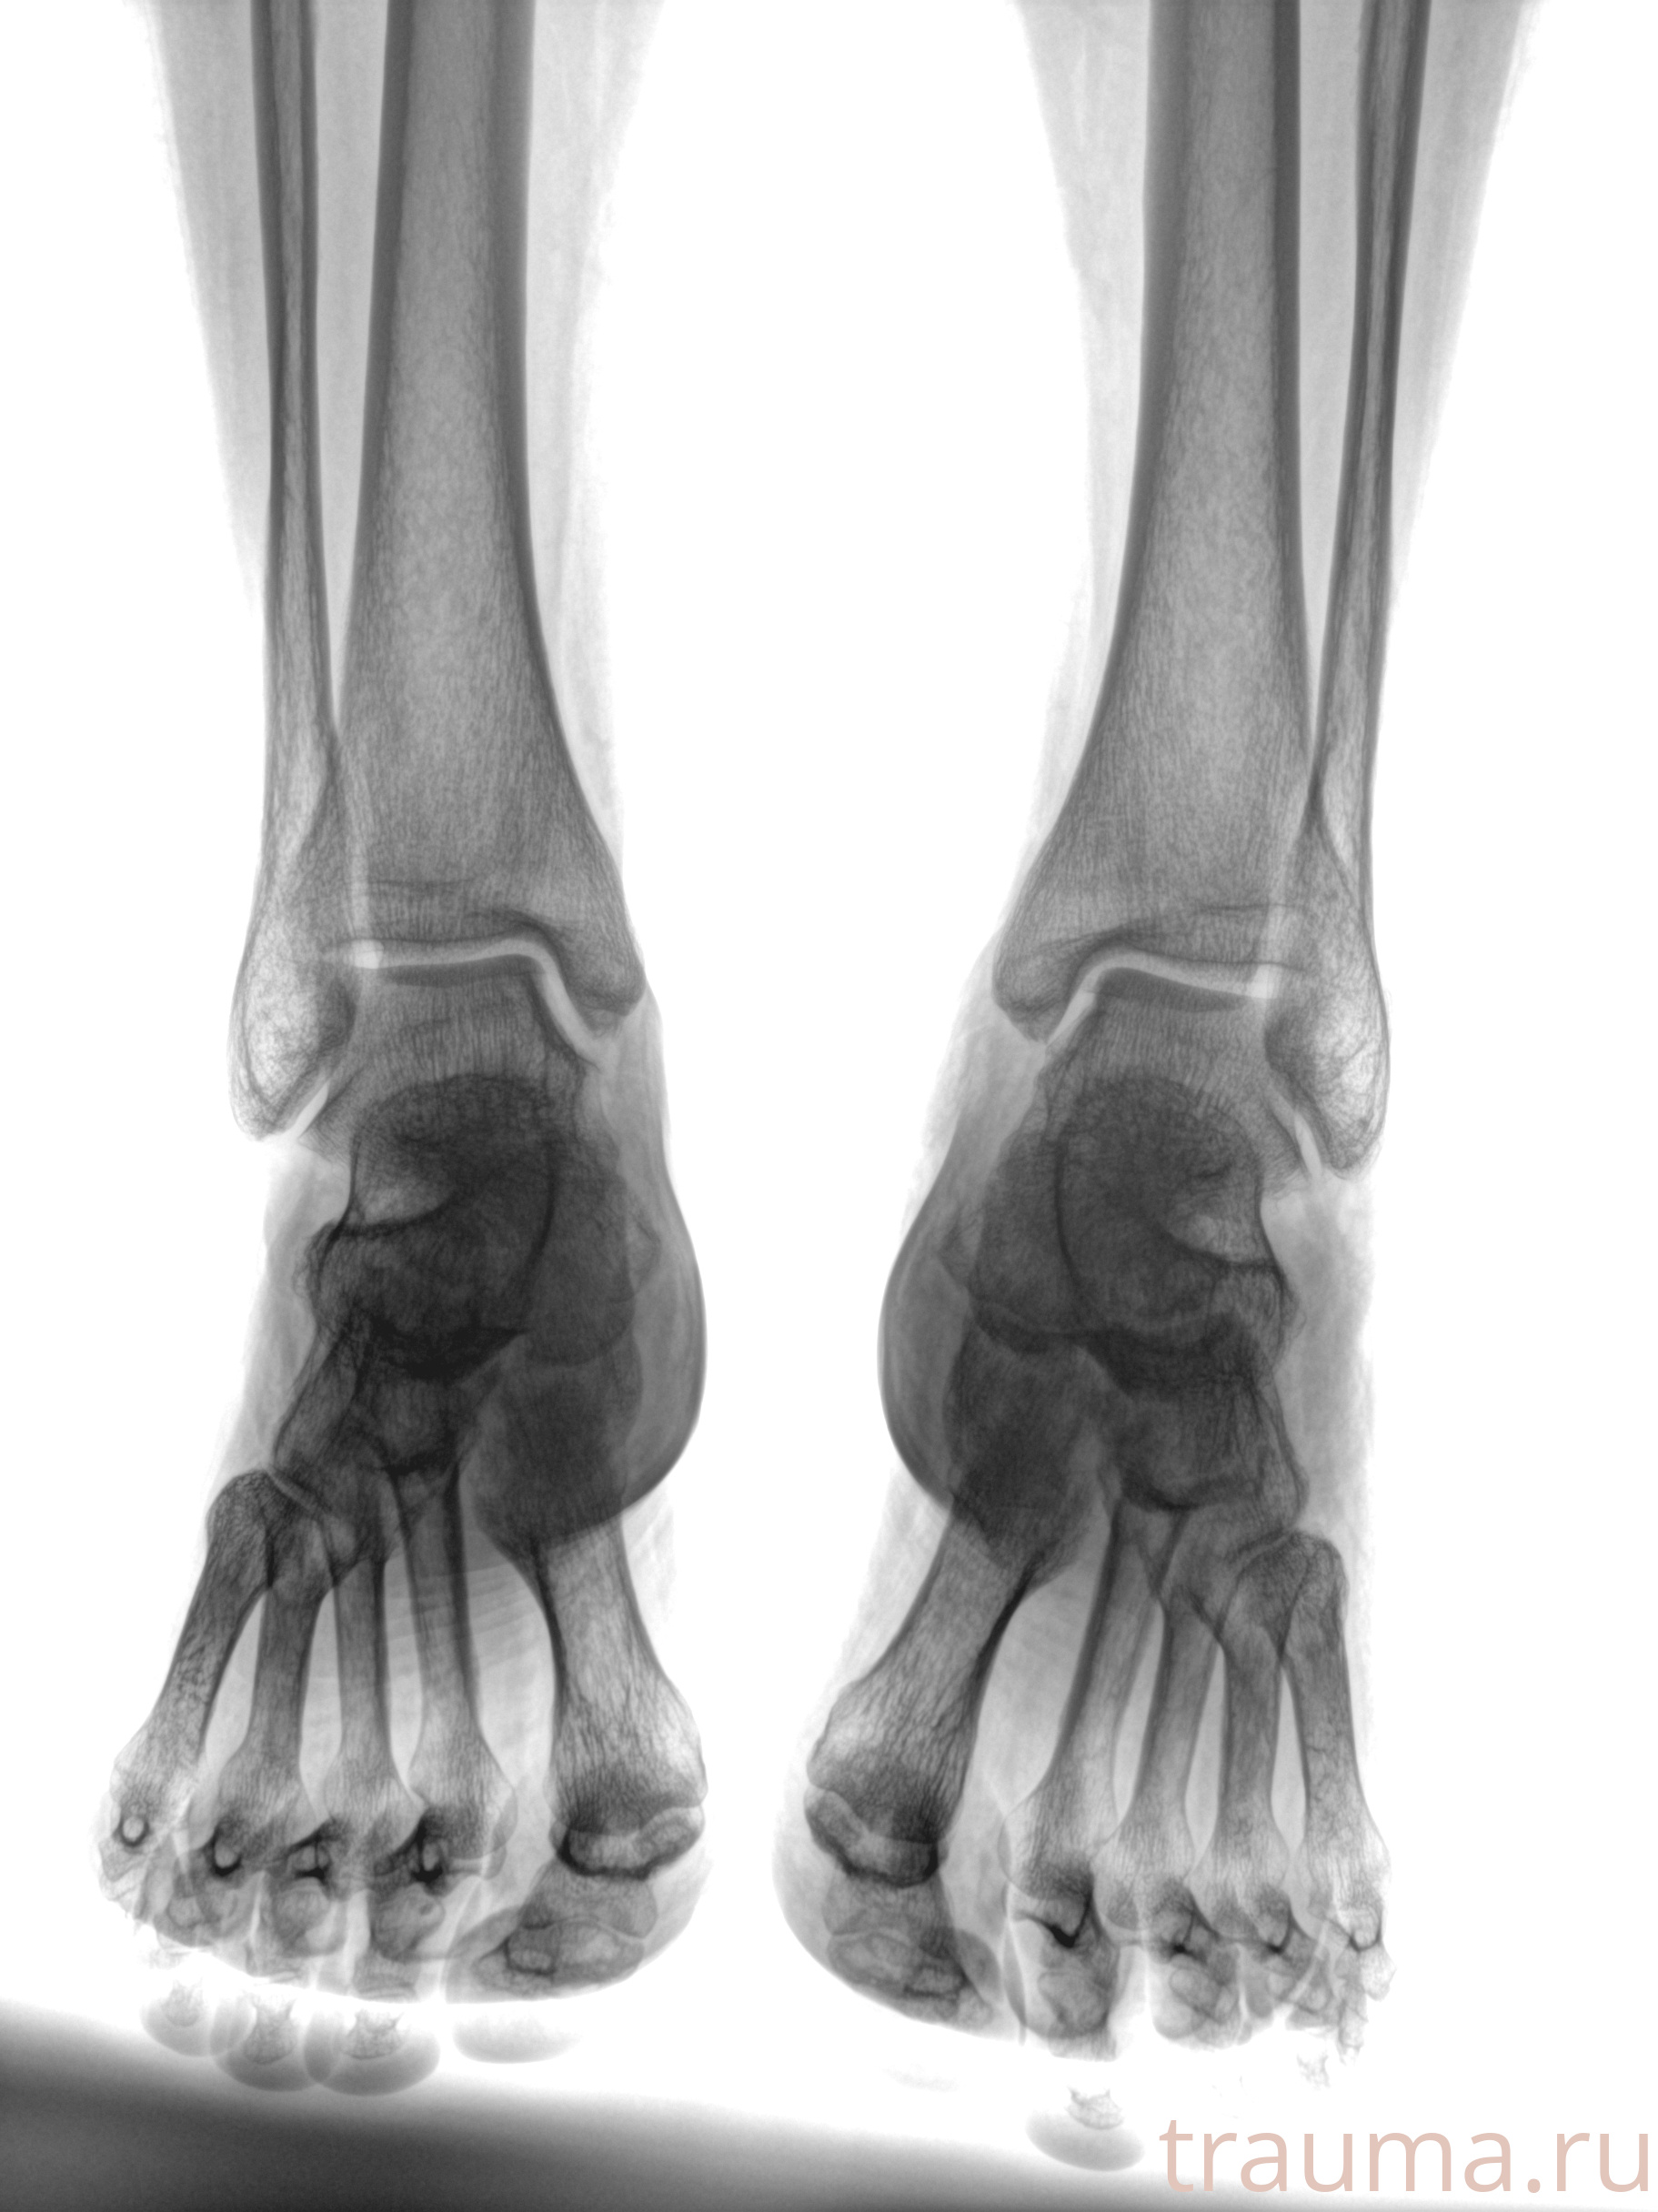

Рентгенограммы

Рентген на дому: по вашему адресу приезжает врач-рентгенолог, травматолог-ортопед с мобильным рентгеновским аппаратом, проводит диагностику травмы или заболевания, делает необходимые рентгенограммы, дает рекомендации по дальнейшему лечению. Получить качественные снимки в домашних условиях возможно благодаря уникальной методике, разработанной МосРентген Центром для института  Склифосовского